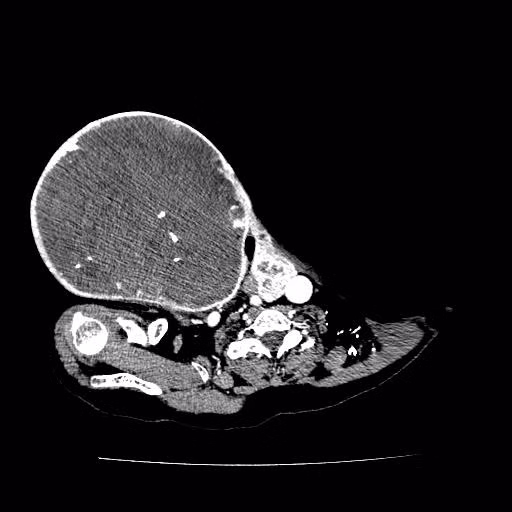

| Phim chụp khối u (BVCC). |

Sau khi được thăm khám và chụp cắt lớp vi tính, bác sĩ cho biết bệnh nhân V.có khối u thùy phải tuyến giáp kích thước 28 x 20 cm.

Theo PGS.TS Lê Văn Quảng cho biết: “Bệnh nhân V. có khối u thùy phải tuyến giáp kích thước rất lớn, tăng sinh mạch máu, đè đẩy khí quản sang bên đối diện, chèn ép động mảnh cảnh, đẩy tĩnh mạch cảnh trong ra ngoài, khối u ở vị trí tập trung nhiều mạch máu quan trọng, u lớn làm tăng sinh mạch máu nên nguy cơ mất máu rất lớn trong quá trình phẫu thuật.Nếu không xử trí tốt có thể gây tổn thương mạch máu lớn, dây thần kinh thanh quản gây khàn tiếng hoặc mở khí quản".

Ca mổ diễn ra thành công, khối u “khủng” đường kính 28 cm, nặng 3,2kg được cắt bỏ hoàn toàn mà vẫn bảo tồn được các dây thần kinh, tuyến cận giáp không tổn thương khí quản, mạch máu lớn.